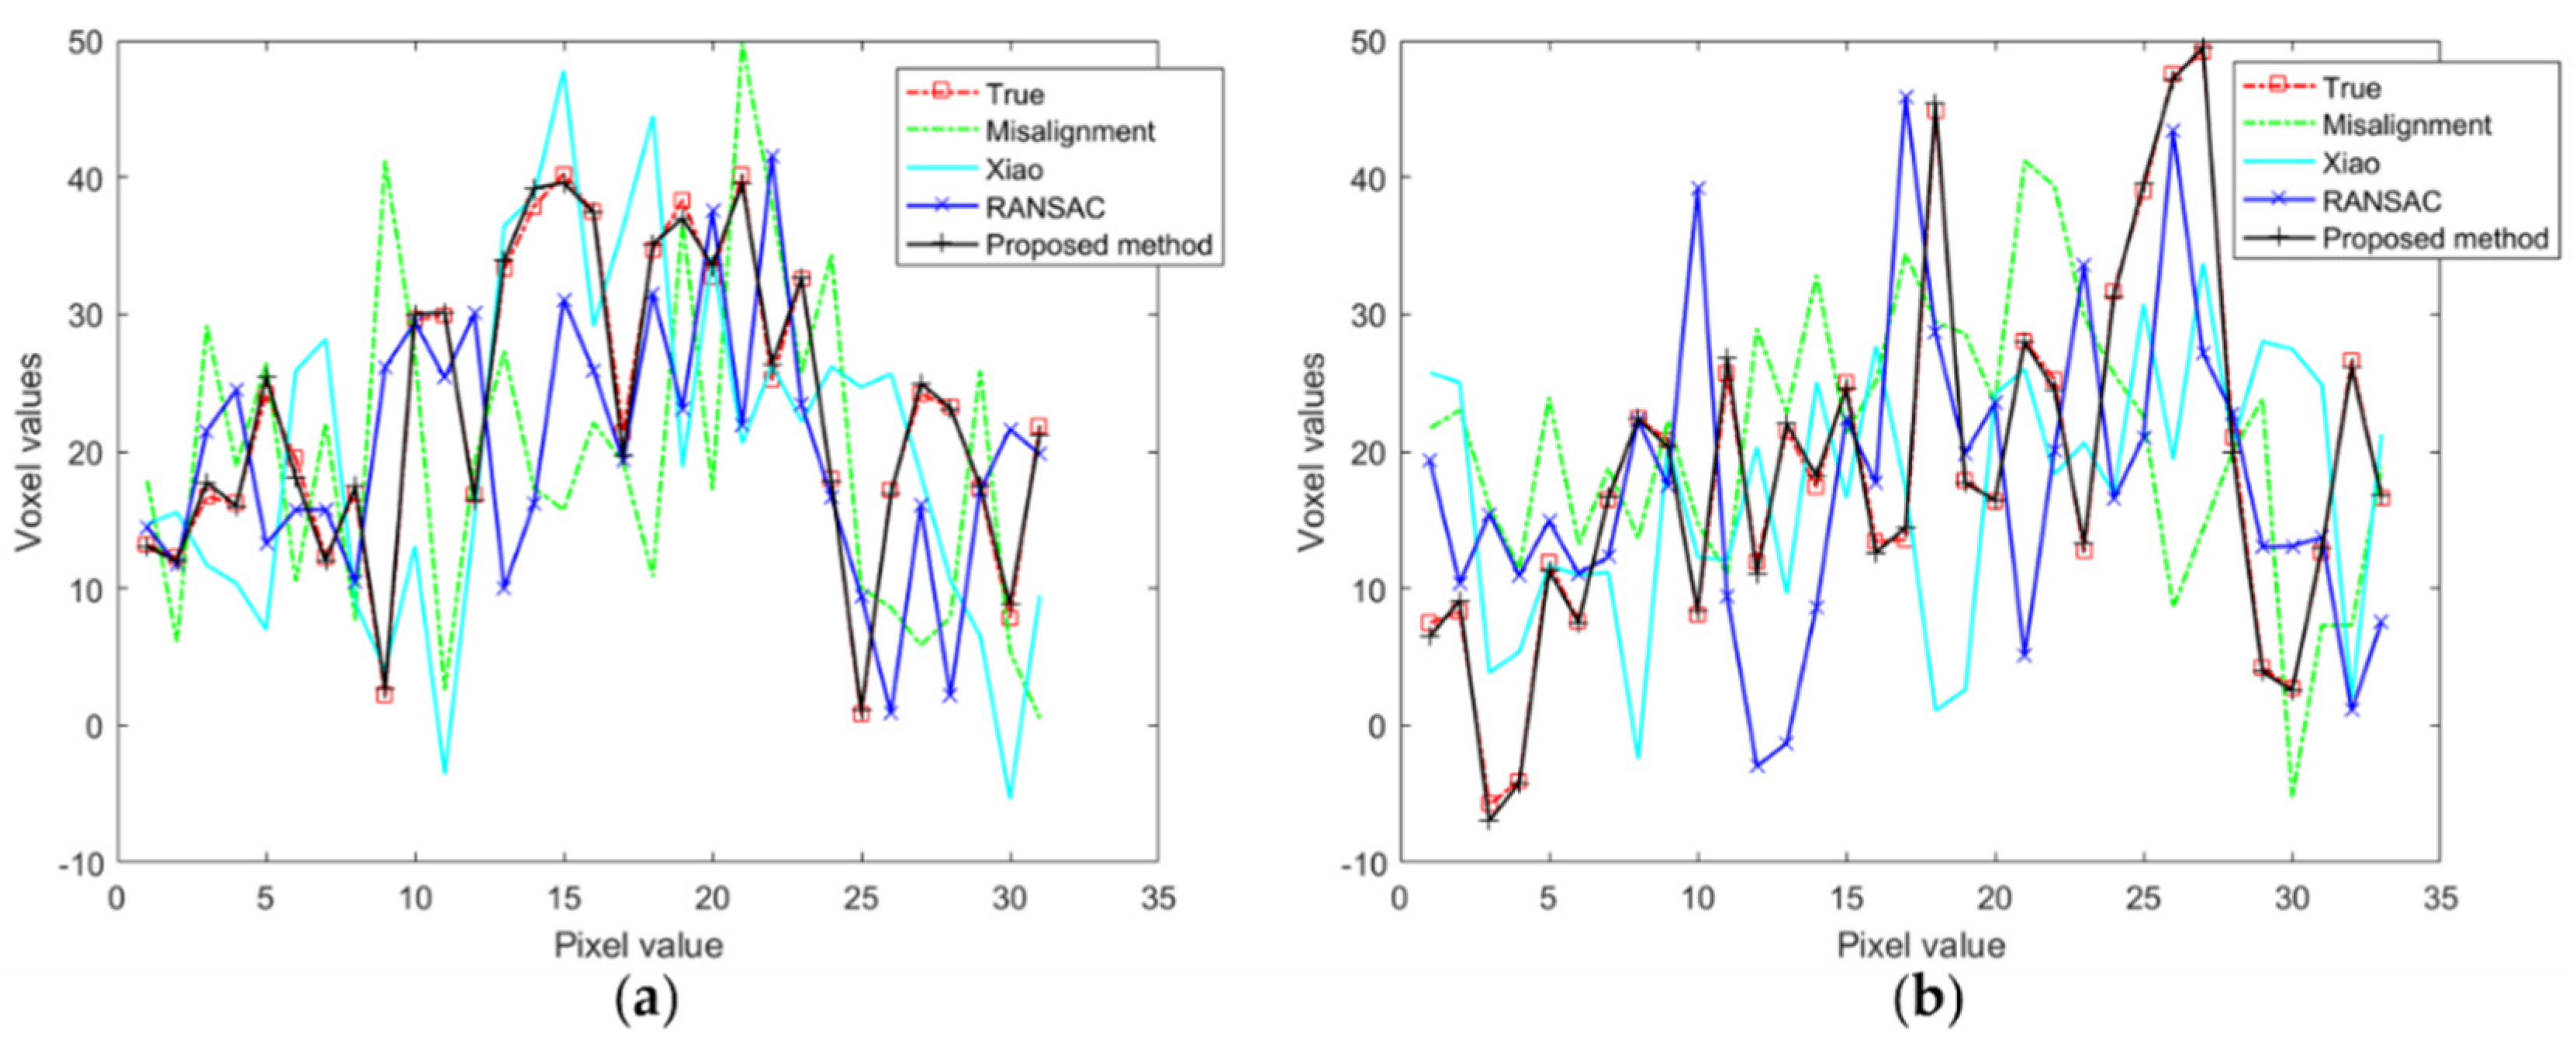

3.1. Simulation Experiments

3.2. Nanotomography Experimental Section